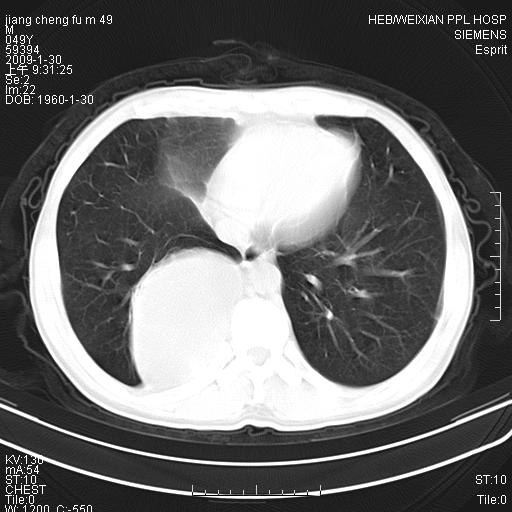

男性,49岁,主因胸痛,右肺呼吸音低。胸片提示肺占位

考虑右侧脊柱旁沟囊性病变。1:支气管囊肿或食管囊;2:神经源性肿瘤。

右后纵隔囊性占位;考虑为:1)淋巴管囊肿。2)食管囊肿。建议:进一步检查。

右后纵隔囊性占位,建议先做增强,后做穿刺活检。

在分析这个病变时,首先病灶边界清晰,但其内密度不均匀,有条索状状实性成分,肿块的外侧壁亦呈一不均匀的厚壁改变,因此支气管囊肿的可能性不大。主要考虑神经源性肿瘤(主要考虑神经鞘瘤,因为它囊变的机率比较高),其次考虑肺膈离征,行增强扫描如发现来自胸主动脉供血动脉血管可确诊。

考虑右侧脊柱旁沟囊性病变,囊骨有分隔,囊壁较厚。1:神经源性肿瘤;2:食管囊肿或淋巴管囊肿。支持!

囊状肿块内有线样软组织分隔,支气管囊肿及食管囊肿可不考虑。我考虑:1、囊性肺膈离征(需要增强扫描来排除)。2、神经鞘瘤。3、淋巴管囊肿。